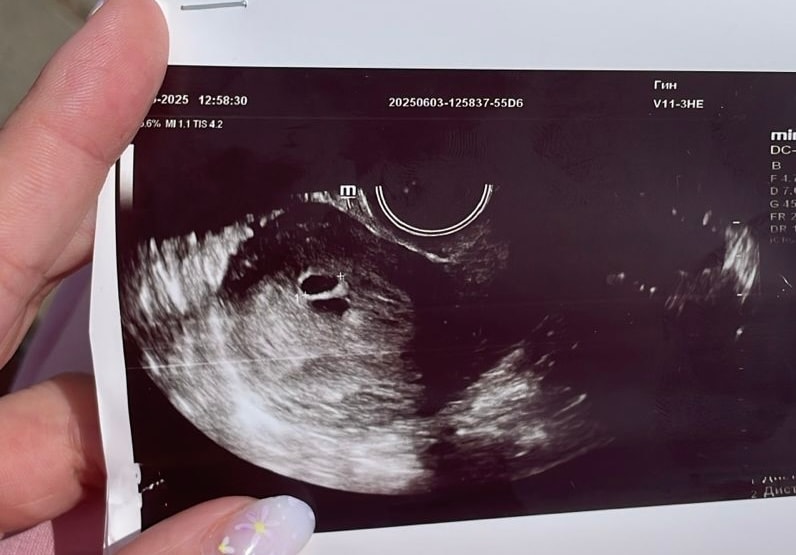

Лариса , как только датчик засунула,врач сразу сказала,а вы знаете что у вас 2 пя,я говорю нет. Потом стала сомневаться,я спросила а это может быть гематома,она сказала,что 100% не гематома,так как внутри нет жидкости,то есть крови. Я говорю,а почему один очерченный,а другой нет. Она сказал,что возможно один может просто отставать в развитии. И назначила контрольное узи через неделю

Евгения, в двух местах была на узи сегодня,нигде не сказали про гематому

Вот узи с перво клиники